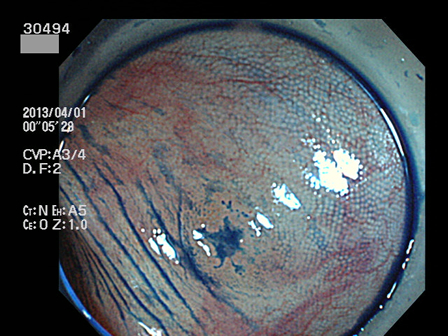

30400 30402 30405 30407 30408 30409 30413 30417 30419 30420 30422 30424 30428 30429 30432 30434 30442 30443 30444 30445 30446 30450 30451 30453 30458 30463 30464 30465 30467 30471 30472 30473 30474 30475 30476 30483 30487 30490 30492 30494 30496 30497 30499・・・・・・・の43名

上記100名より抽出した平坦・陥凹型腺腫(=癌化の危険が高いが見落としやすい病変)の内視鏡写真